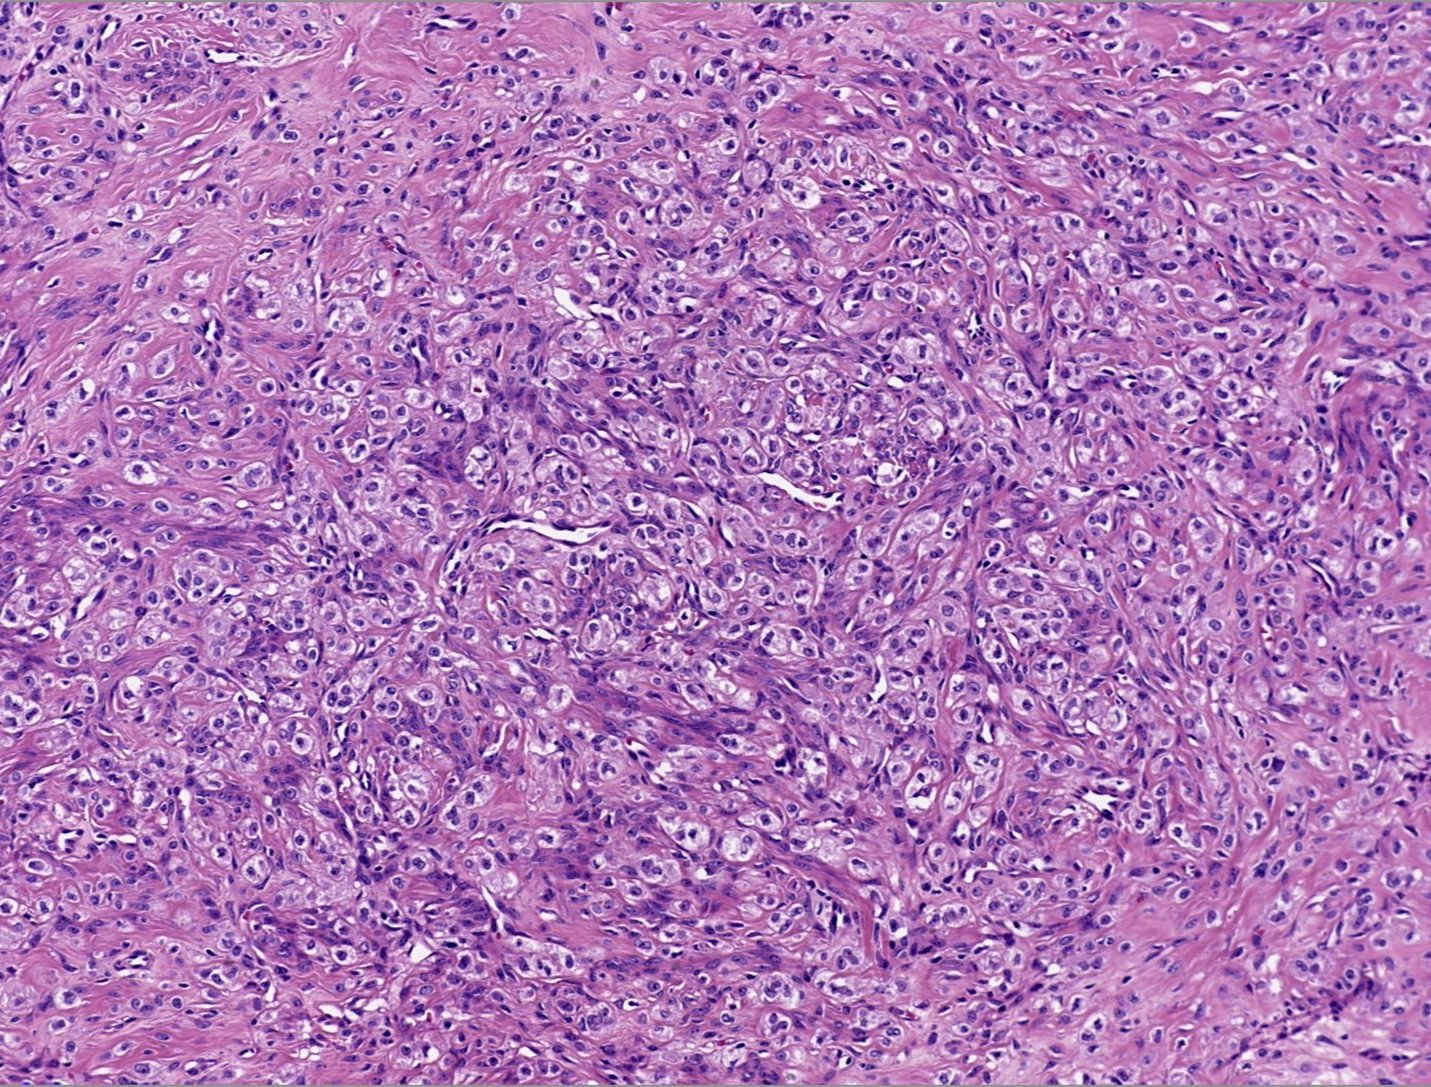

- Pseudolobules comprised of a jumbled admixture of epithelioid (lutein) and spindled cells with minimal atypia

- Epithelioid cells: round nuclei with prominent nucleoli, vesicular chromatin and clear to vacuolated cytoplasm

- Abundant eosinophilic cytoplasm often seen in pregnancy (Int J Gynecol Pathol 2015;34:357)

- Occasionally have a signet ring-like appearance

- Spindled cells: elongated nuclei with indistinct nucleoli, bland chromatin and scant eosinophilic cytoplasm

- Typically round to ovoid but may show angulation if edema is striking

- Epithelioid cells: round nuclei with prominent nucleoli, vesicular chromatin and clear to vacuolated cytoplasm

- Mitoses are often inconspicuous but rarely can be up to 12/10 high power fields, no atypical forms (Int J Gynecol Pathol 2016;35:549)

Microscopic (histologic) images